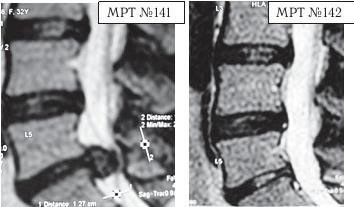

На МРТ № 141 наблюдается состояние поясничного отдела позвоночника: секвестрированная грыжа межпозвонкового диска в сегменте LV-SI, абсолютный стеноз спинномозгового канала.

На МРТ №°142 — состояние поясничного отдела позвоночника данного пациента после лечения методом вертеброревитологии: отсутствует грыжа межпозвонкового диска в сегменте LV-SI, более того, наблюдается активизация репаративного процесса в межпозвонковом диске данного сегмента.

Состояние данного пациента было тяжёлым, в течение двух месяцев боли не купировались и он практически не спал. Нейрохирурги настаивали на срочной операции и были правы: показания к операции в данном случае — 100 %. Но пациент испытывал сильное беспокойство и страх по этому поводу, так как после аналогичной операции его родственник утратил способность к самостоятельному передвижению, стал инвалидом и потерял доходную работу. Ну что поделаешь, если человек был свидетелем таких печальных последствий, как говорится в пословице, — только слепой не боится призраков. Как врачи ни объясняли сложность его ситуации, пациент упорно не хотел оперироваться, а лекарства уже практически не действовали. Но нейрохирурги ведь тоже люди, терпение у них хоть и большое, но не «железное». В результате они дали пациенту адрес клиники вертеброревитологии. Как оказалось впоследствии, эта попытка нейрохирургов помочь пациенту была поистине их «соломоновым решением».